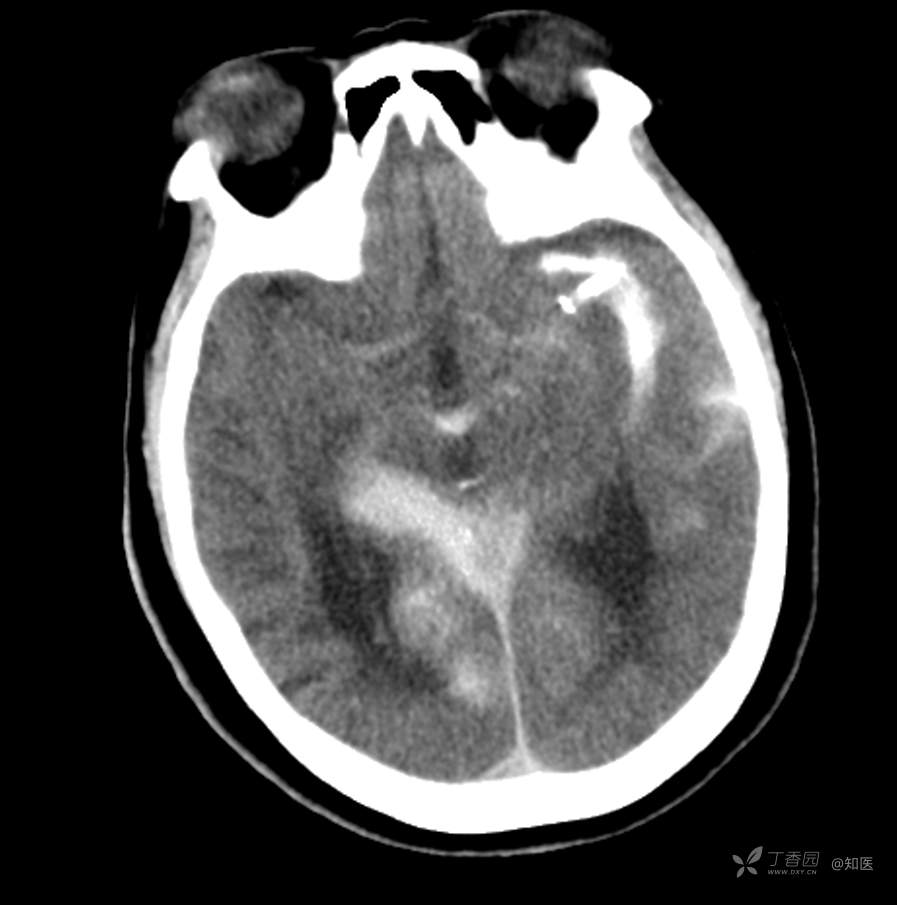

4-22日查房患者呈昏睡状,混合性失语,右侧肢体肌力障碍较入院时加重,胃肠减压引流物为深黄绿色液体,量约150ml。查体:GCS 9分(睁眼反应 3分+语言 1分+运动 5分),NHISS评分23分(意识水平 2分+提问 2分+指令 1分+凝视 2分+面瘫2+左上肢 1分+右上肢4分+左下肢 2分+右下肢4分+语言 3分),昏睡状,查体欠合作,混合性失语,粗测智能查体不配合。双眼闭目紧,双侧球结膜水肿,双侧瞳孔等大等圆,直径约4.0mm,对光反射灵敏,眼球无自主运动,无眼震,右侧鼻唇沟浅,口角向左歪斜。咽部查体不配合。转颈、耸肩查体不配合。伸舌不配合。右上肢肌力1级,右下肢肌力2级,左上肢肌力3级,左下肢肌力4级,四肢肌张力减低。四肢深浅感觉及共济运动查体不配合。右侧巴氏征阳性,左侧巴氏征阴性。颈抵抗。双侧布氏征及克氏征均阴性。辅助检查:头颅+胸部CT:与前片(2021-4-21 13:57)对比,现片示:1、环池、桥前池及大脑镰后部及小脑幕高密度影,考虑出血,较前新发。2、额颞顶叶高低混杂密度影,考虑梗塞伴造影剂残留;左侧大脑中动脉走行区致密影,系术后改变;请结合临床。3、多发腔梗,脑白质脱髓鞘,脑萎缩。4、双肺间质性改变,双肺下叶纤维索条,双侧胸腔微少量积液征象,双侧胸膜增厚。5、主动脉及冠状动脉管壁多发钙化斑块。三线主任医师、二线主治医师查房后示:根据患者病史、体征及辅助检查,目前诊断:1.脑梗死出血转化;2.左侧大脑中动脉次全闭塞;3.左侧大脑中动脉支架植入术后;4.高血压2级(很高危);5.2型糖尿病;6.应激性溃疡伴出血。目前病情及治疗上需注意以下问题:1.患者出血转化,增加脱水剂剂量,调整为20%甘露醇 125ml 每8小时一次、甘油果糖 250ml 每12小时一次,同时结合患者球结膜水肿,白蛋白正常低值,今日给予补充人血白蛋白10g,注意监测电解质等变化。2.患者为蛛网膜下腔出血,给予泵入尼莫地平预防脑血管痉挛。3.患者左侧大脑半球见大片脑白质脱髓鞘,考虑脑白质营养不良,给予维生素B1、维生素B12、维生素C、维生素B6及依达拉奉改善微血管通透性;4.患者出现应激性溃疡伴出血,今日暂禁食,给予泮托拉唑抑酸及肠外营养补充,密切观察消化道出血情况,根据病情变化调整抑酸药物剂量及频次;5.患者卧床,今晨见明显痰多,给予化痰等对症处理,监测血常规及脓毒症2项指标。6.向家属再次告知病情,因患者高龄、既往高血压及糖尿病病史,此次治疗出现出血转化,存在意识障碍加深、病情加重可能。7.密切观察神经系统体征变化。遵嘱执行。

4-23日查房:患者呈中度醒状昏迷,右侧肢体肌力障碍较入院时加重,胃肠减压引流物为黄绿色液体,量约200ml。入院后至今晨入量为4050ml,出量为4850ml。查体:GCS 6分(睁眼反应 2分+语言 1分+运动 3分),NHISS评分35分(意识水平 3分+提问 2分+指令 2分+面瘫3分+左上肢 4分+右上肢4分+左下肢 4分+右下肢4分+感觉 2分+语言 3分+构音障碍 2分+忽视 2分)。中度昏迷。双目睁眼状,双侧球结膜水肿较昨日明显,双侧瞳孔等圆,不等大,右侧直径约3.5mm,左侧瞳孔直径约3.0mm,对光反射灵敏,眼球无自主运动,无眼震。右侧鼻唇沟浅,口角向左歪斜。咽部查体不配合。转颈、耸肩查体不配合。伸舌不配合。四肢肌力检查不配合,右上肢落鞭征阳性,左上肢落鞭征阴性,右下肢不能撑于床面,左下肢可撑于床面,四肢肌张力减低。四肢深浅感觉及共济运动查体不配合。右侧巴氏征阳性,左侧巴氏征阴性。颈抵抗。双侧布氏征及克氏征均阴性。辅助检查:经颅多普勒示:左侧大脑中动脉峰值流速极低,右侧大脑中动脉及双侧大脑前动脉血流速度未见明显异常。头颅CT(2021-04-22):与前片(2021-4-21)对比,现片示:1.环池、桥前池及大脑镰后部及小脑幕高密度影,较前减少。2.额颞顶叶高低混杂密度影,考虑梗塞伴造影剂残留;左侧大脑中动脉走行区致密影,系术后改变;基本同前。请结合临床。3.多发腔梗,脑白质脱髓鞘,脑萎缩。同前。二线主治医师查房后示:患者目前诊断明确。现治疗上需注意以下问题:1.患者夜间体温上升,最高38度,结合患者卧床、痰多、不易咳出,且化验检查提示炎性指标较前明显升高,今日给予头孢哌酮舒巴坦抗感染治疗,同时继续雾化祛痰等。2.因患者应激性溃疡并出血,昨日查胃液潜血阳性,但经给予泮托拉唑抑酸护胃治疗后消化道出血未进行性加重,胃管引流物为黄绿色液体,今日暂继续给予氨基酸、脂肪乳等肠外营养支持,安排再次复查胃液潜血,若转阴可给予肠内营养加强支持治疗。3.患者血压仍有偏高,夜间泵入乌拉地尔控制,今日给予左氨氯地平平稳控制血压,监测血压变化。4.患者昨日血糖波动在6.8-11.4mmol/l,结合其糖化血红蛋白为6.4%,暂不干预血糖,继续监测血糖变化。5.患者意识障碍程度加重,双侧瞳孔不等大,但光反射灵敏,考虑与脑梗死后水肿高峰有关,治疗上继续加强脱水,向家属再次详细告知病情及目前诊疗方案,存在颅内压增高至脑疝形成、呼吸心跳骤停可能,表示理解知情。密切观察生命体征及神经系统体征变化。遵嘱执行。